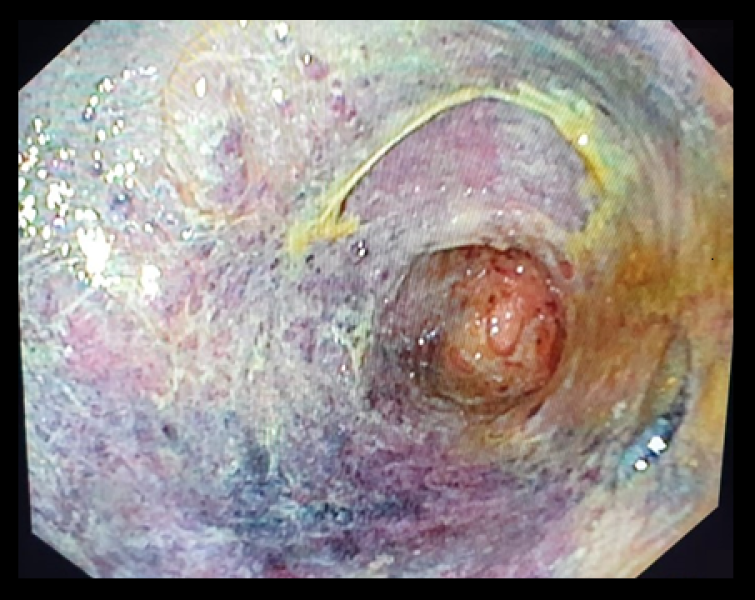

An uninvited guest

Fotografia